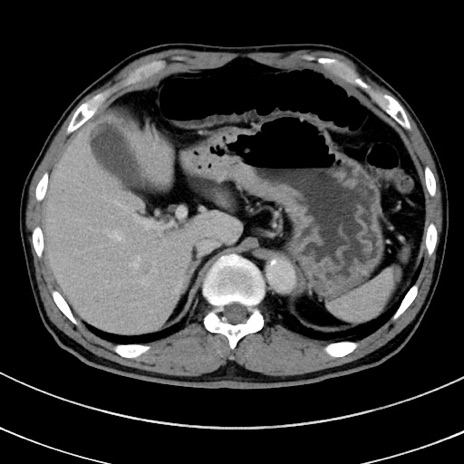

症例8(横断像)

【症例】 60歳代男性

【主訴】 黒色吐物

【現病歴】 4日前から嘔気自覚、2日前の朝食後にも嘔気あり、自分で手で嘔吐反射起こし嘔吐したところ血が混ざっていたため受診。

【既往歴】 5年前汎発性腹膜炎を伴う急性虫垂炎で手術、高血圧、前立腺肥大症、高脂血症

【身体所見】 腹部正中に手術癩痕あり 腹部平坦・軟圧痛なし膨満感あり

【データ】WBC 8400、CRP 4.54